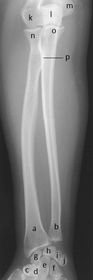

A. proximal radioulnar joint B. olecranon process C. coronoid process D. coronoid tubercle E. body/shaft F. ulna G. ulnar notch H. head I. styloid process J. distal radioulnar joint K. styloid process L. radius M. body/shaft N. radial tuberosity O. neck P. head Q. radial notch (on ulna)

a. radius b. ulna c. trapezium d. trapezoid e. capitate f. hamate g. scaphoid h. lunate i. triquetrium j. pisiform k. capitulum l. olecranon process m. medial epicondyle n. radial head o. coronoid tubercle p. radial tuberosity